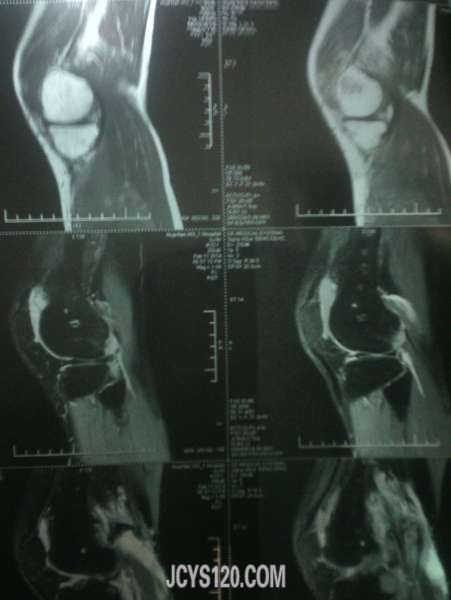

患者33岁男 因路滑扭伤!随即到医院检查,一般情况尚可,右侧膝关节。小腿腹部肿胀疼痛,磁共振影像如下,手机拍摄不是那么清楚!愿个为同行给点建议!需要做关节腔镜手术吗?有没有什么处理的方法给说说!!!

这种核磁影像不是熟悉,希望影像版版主给看看,或者楼主干脆把报告单一并发上来!

谷维素 发表于 2014-2-12 18:44 static/image/common/back.gif 这种核磁影像不是熟悉,希望影像版版主给看看,或者楼主干脆把报告单一并发上来! 谢谢回复!我也是看不太明白!毕竟见的太少~忘高手赐教!!!!

膝关节外力引起的损伤,较轻是以皮肤肌肉肌腱的损伤,严重时则出现半月板撕裂伤,髌骨的骨折。对于皮肤肌肉肌腱的损伤给予常规治疗即可,当出现半月板撕裂伤时可采取半月板的修补或切除术,这些度需要在关节镜下完成,髌骨骨折一般采用功能位的石膏固定。

体检下前后交叉韧带,侧副韧带有没有损伤,膝关节正侧位X片就够了,小腿后腹部肿明显一般是腓肠肌损伤,检查下跟腱有没有损伤,如果有问题再分别撕裂伤还是断裂伤,按情况相应处理,单肿胀用消炎止痛软胶外敷3-5天就可以了。大医院很多检查浪费。。。

片子看不懂,如果没有其他,肿胀是外伤导致静脉回流不畅所致,静滴几天丹参和七叶皂苷钠好的快些。

片子看不懂,患者没有住院。我们可以小心的给与云南白药,龙血竭胶囊治疗,但要注意观察。